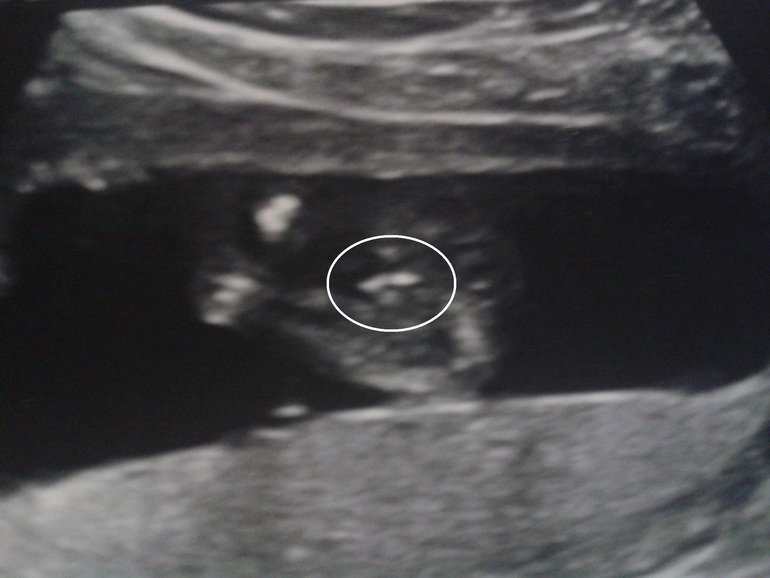

В пузе у меня. Че то как то напрягает((( то активничал,пинался постоянно, а перед сном моим так вообще буянил...и после сладкого тоже...а вчера весь день тишина,абсолютная...Под ночь легла и слушаю.... пихнулся пару раз,успокоить меня видимо. И опять тишина. До сих пор молчит. С самого утра. Что за резкая тишина такая? на узи была неделю назад,все хорошо с малышом, только плацента преждевременно стареет. 28 недель ровно. Нервничаю(

это что?)))